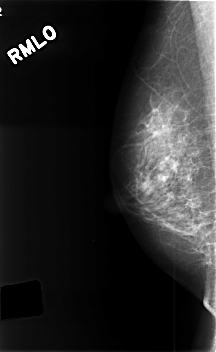

C_0385_1.RIGHT_MLO

RIGHT_CC LINES 4560 PIXELS_PER_LINE 2776 BITS_PER_PIXEL 12 RESOLUTION 50 NON_OVERLAY

RIGHT_MLO LINES 4576 PIXELS_PER_LINE 2808 BITS_PER_PIXEL 12 RESOLUTION 50 NON_OVERLAY